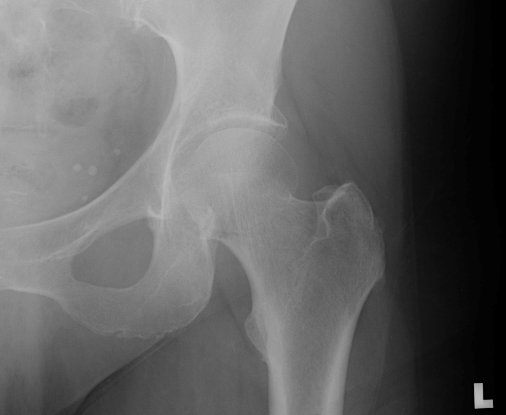

Return to Proximal Femur Fracture